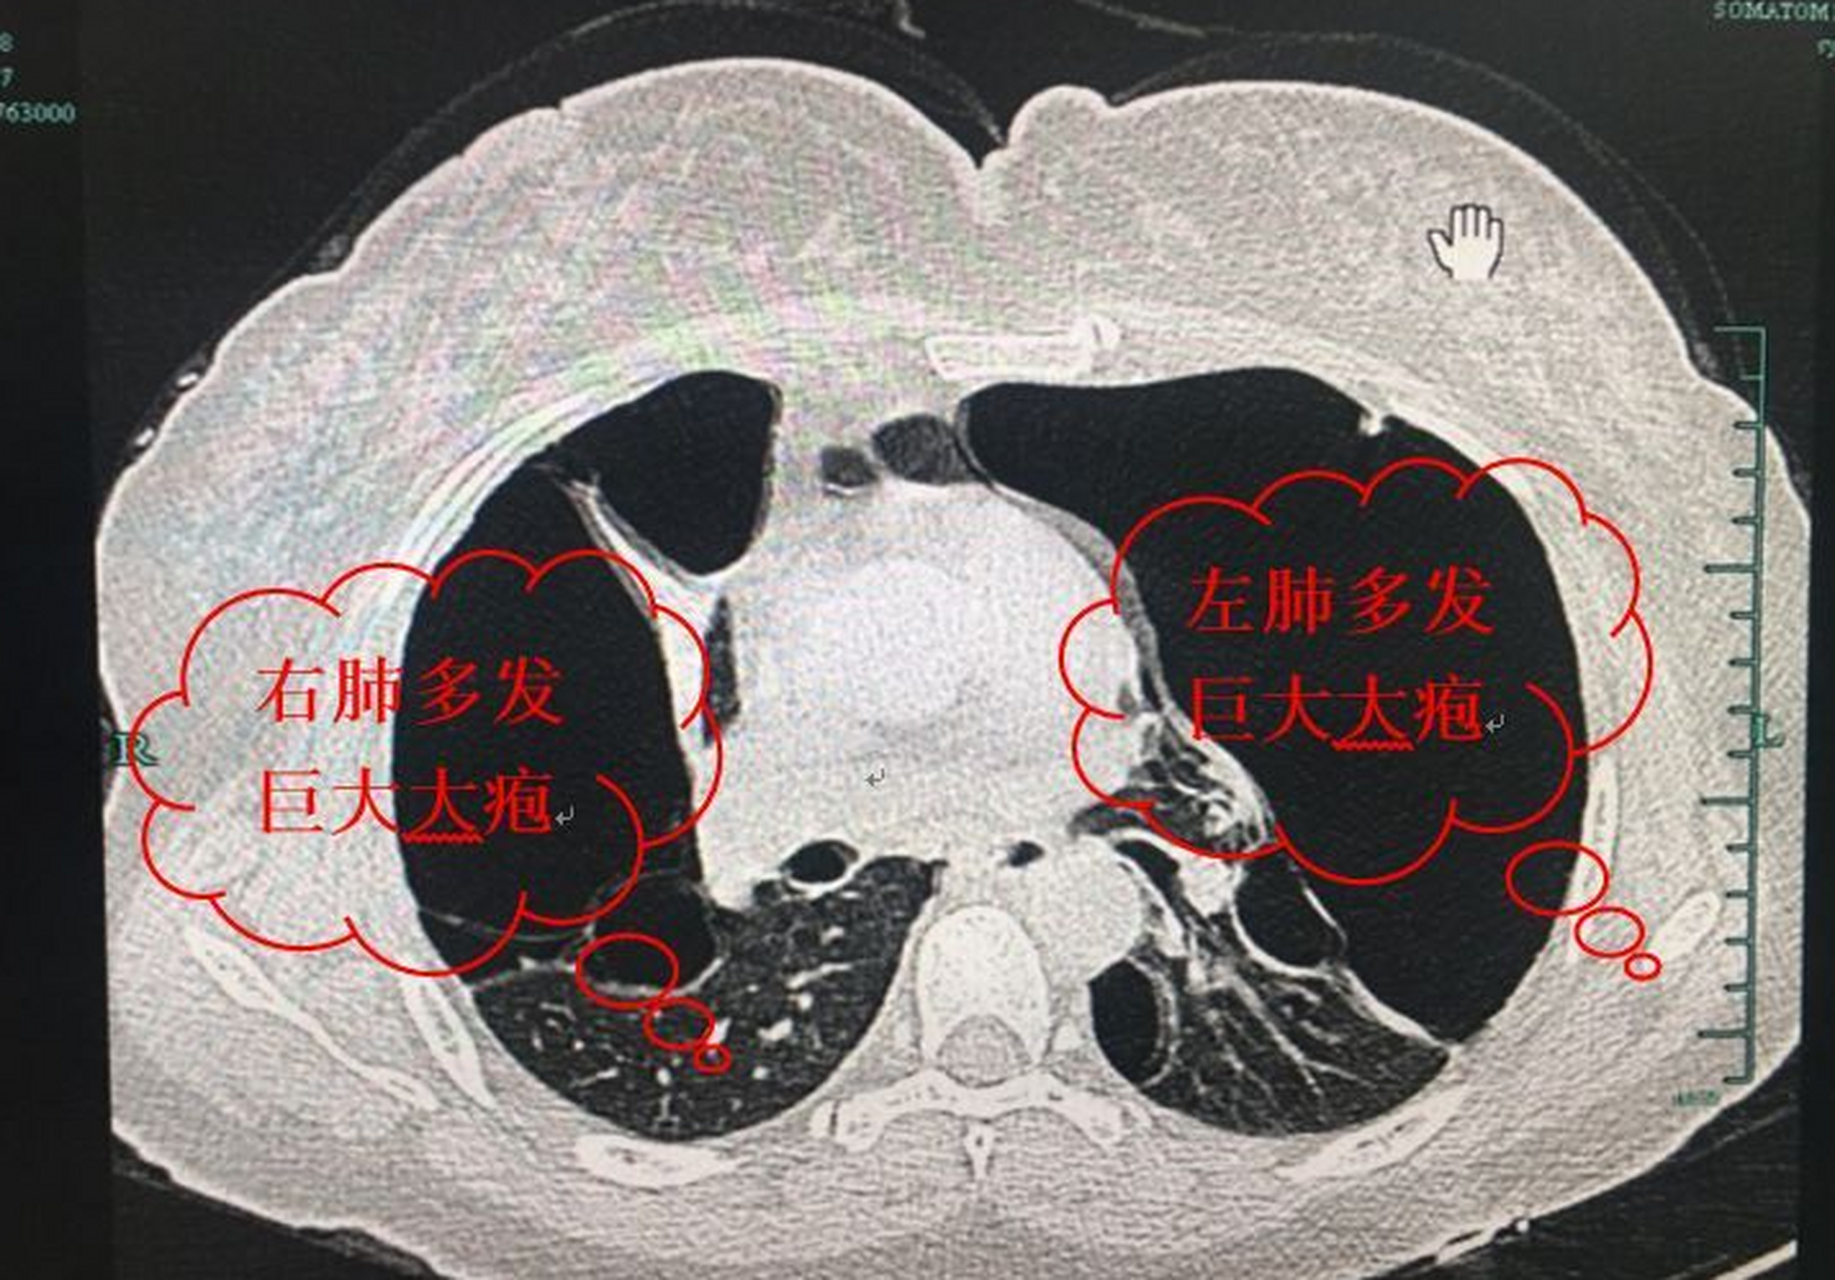

有些患者还在跟我问肺大泡,肺气肿,慢阻肺,是不是要戒烟戒酒!